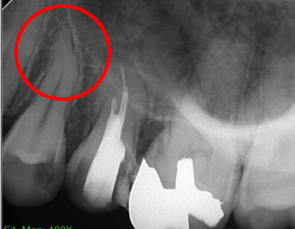

根管治療前後のレントゲン写真

| 治療前 | 治療後 |

|---|---|

![]() |

上記の流れに沿って治療を行い、根管内の消毒を十分に実施した上で根の先まで薬剤を充填しました。